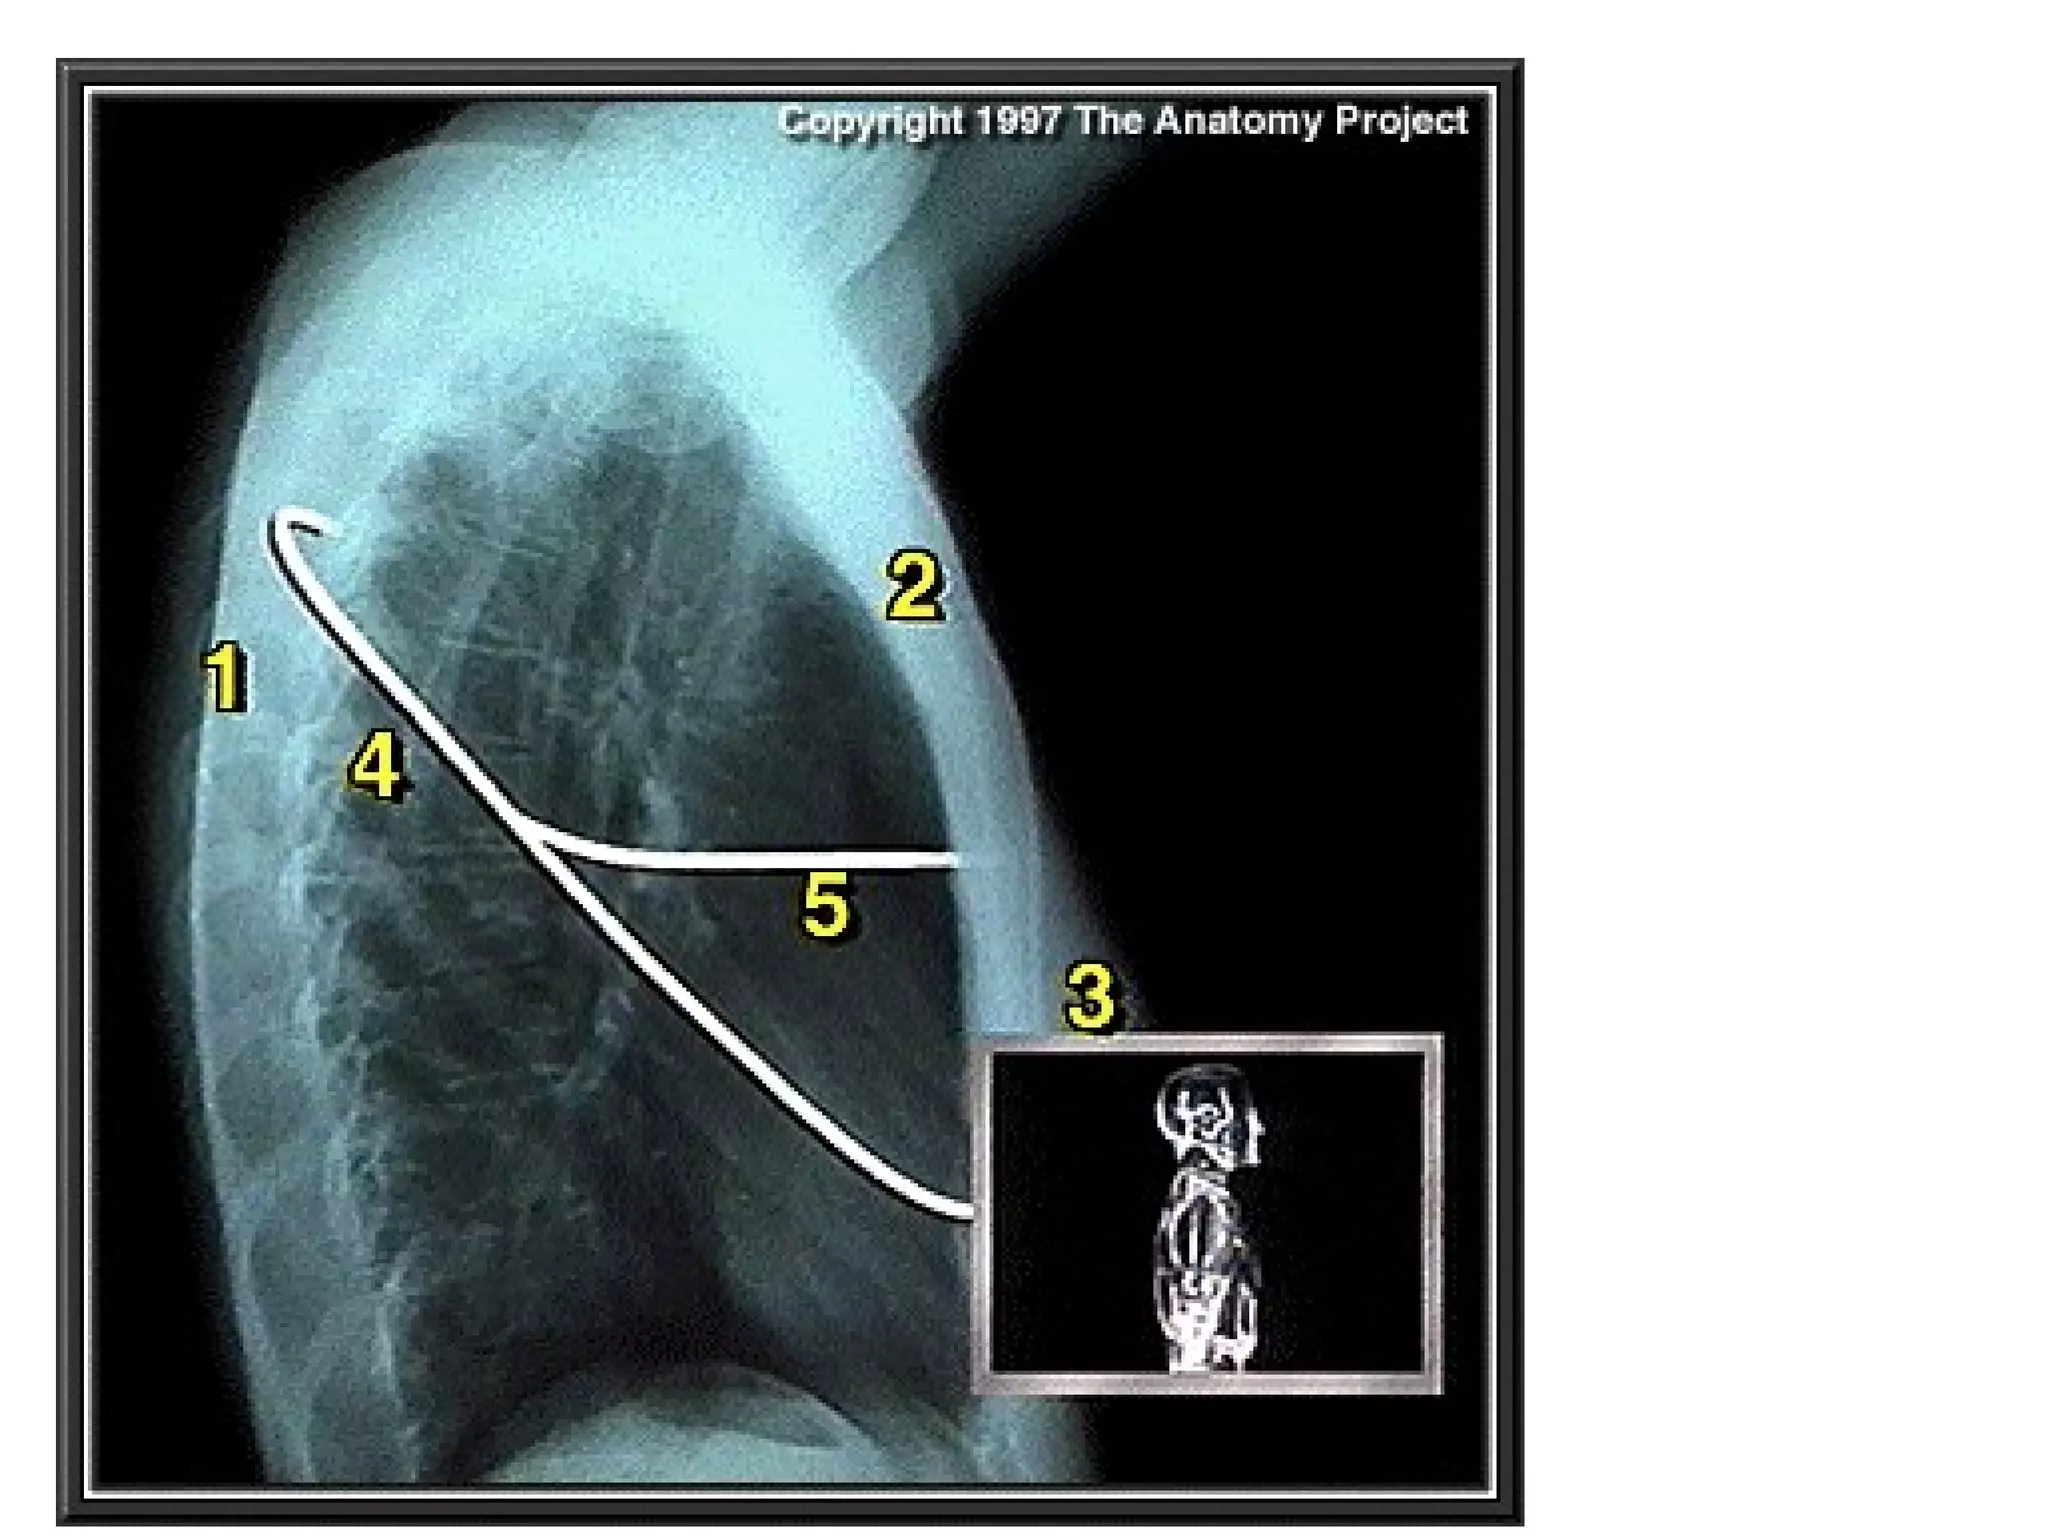

The fissures

The main fissures

The horizontal fissure is seen often incompletely

on PA film

The oblique fissures are seen on lateral film

commence posteriorly at the level of T4 or T5

passing through the hilum. The left is steeper

and finishes 5cm behind the anterior

costophrenic angle, where as the right ends just

behind the angle.

The fissures The mainfissures The horizontal fissure is seen often incompletely on PA film The oblique fissures are seen on lateral film commence posteriorly at the level of T4 or T5 passing through the hilum. The left is steeper and finishes 5cm behind the anterior costophrenic angle, where as the right ends just behind the angle. Accessory fissures, the azygos fissure is comma shaped and nearly always right sided.